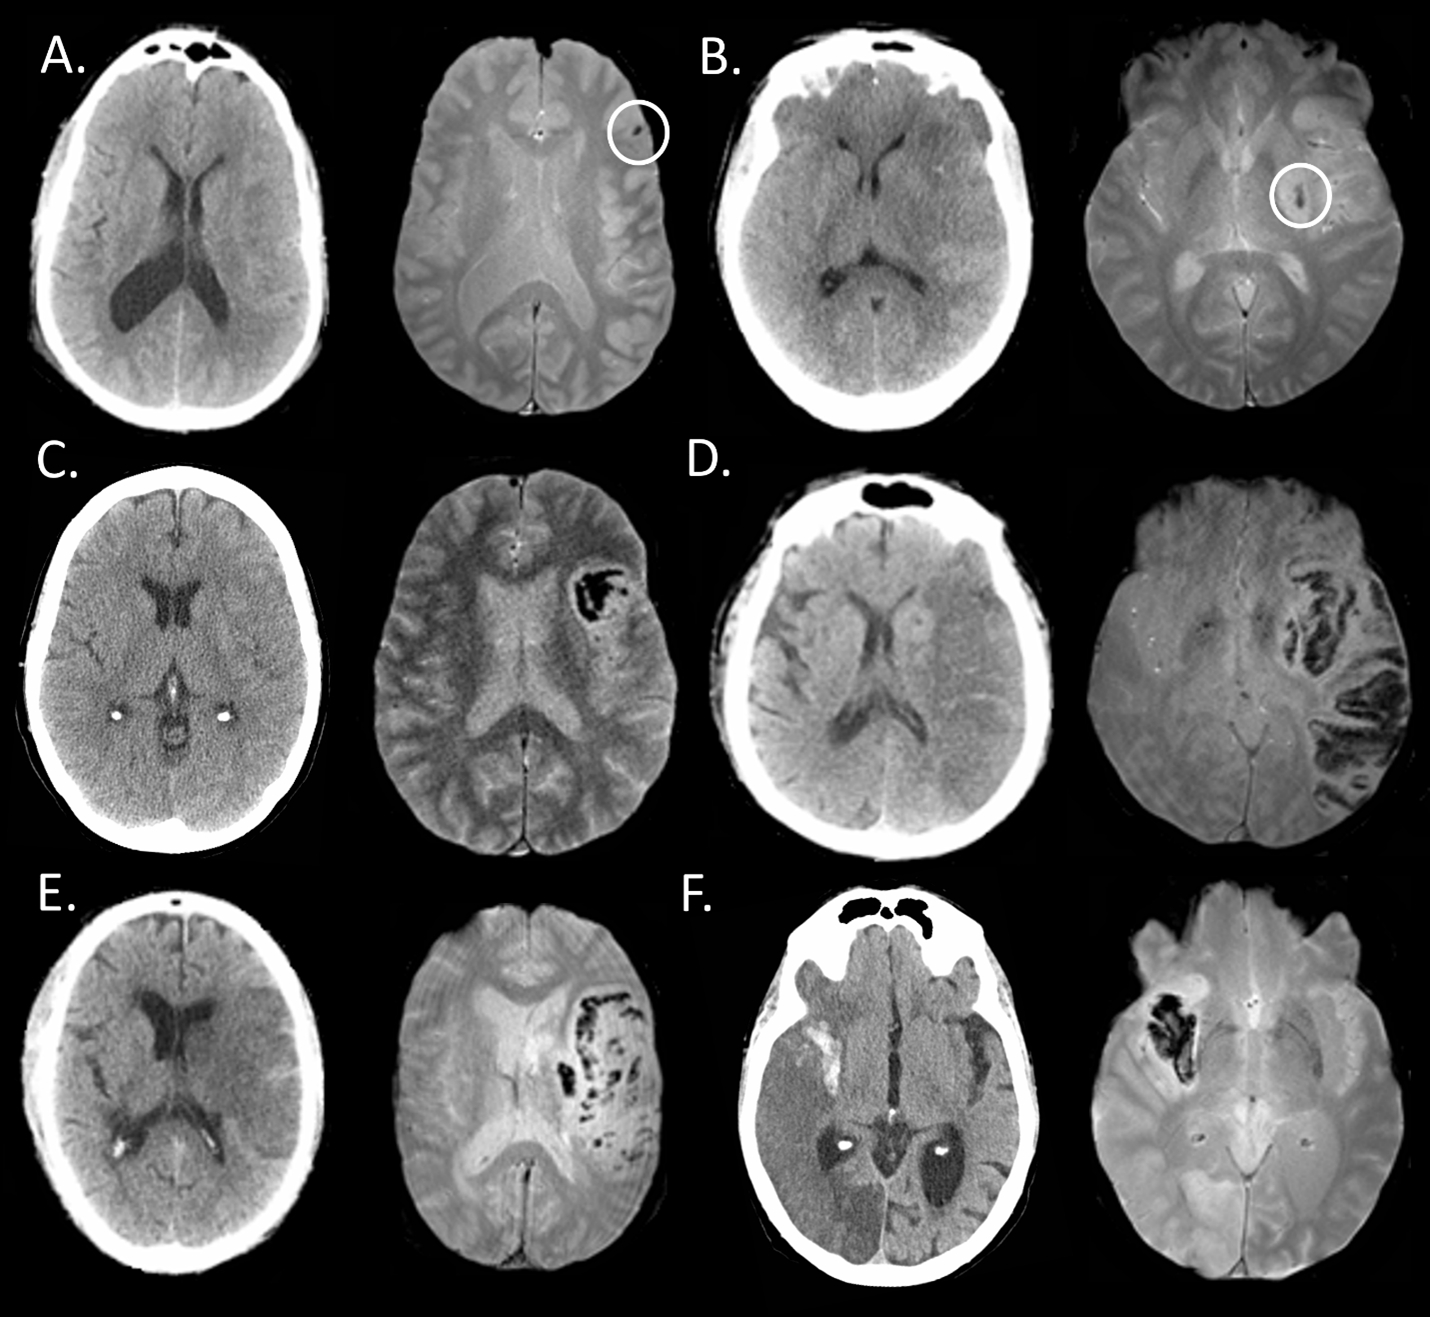

Comparison of HEmorrhage on CT versus MRI After ThrombEctomy: The HECATE study

The characterization of hemorrhage following acute stroke intervention has largely been CT-based. We sought to compare MRI- and CT-based scoring of hemorrhage after acute endovascular therapy (EVT) applying the Heidelberg Bleeding Classification (HBC) to assess inter-modal agreement and quantify inter-rater agreement.

Consecutive acute stroke patients were included in this retrospective study if they: i) had MRI and CT ≤12 hours of each other OR ii) had CT bracketed by MRI pre- and post-CT [i.e. MRI-CT-MRI] ≤7 days post-EVT. The concordance of the HBC ratings by consensus panel were compared between CT and T2*GRE MRI.

For the 87 EVT-treated patients included, median age was 68 years [60-74], admit NIHSS 18 [13-23], 47% were treated with IV/IA thrombolytics, and 93% were successfully recanalized (mTICI 2b/3). Hemorrhage was detected on at least one modality in 60% (52/87) of patients. We found a 68% (59/87, 95% CI [57-77%]) agreement overall between CT and MRI for hemorrhage classification post-EVT. MRI had the best inter-rater agreement for HBC 0 (no hemorrhage) with excellent concordance (κ=0.882), compared to CT (κ=0.683). T2*GRE MRI tended to have increased sensitivity to scattered petechial hemorrhage (HBC 1a) as compared to CT with 17% (2/12) inter-modal agreement. The inter-rater agreement of HBC class 2 (i.e. PH-2) was substantial for MRI (κ=0.781) and excellent in CT (κ=0.951), with 67% (8 /12) inter-modal agreement. SAH was detected in 24% (21/87) of patients on CT and/or MRI with 29% (6/21) inter-modal agreement.

With the exception of SAH and minor petechial hemorrhagic transformation, we found that MRI and CT are overall interchangeable for detecting and classifying hemorrhage after endovascular therapy, reassuring findings for both clinical-decision making and research application. Given the complexity of hemorrhage subtypes post-EVT, work to further refine a post-EVT hemorrhage classification scale with clinical correlation would be beneficial.